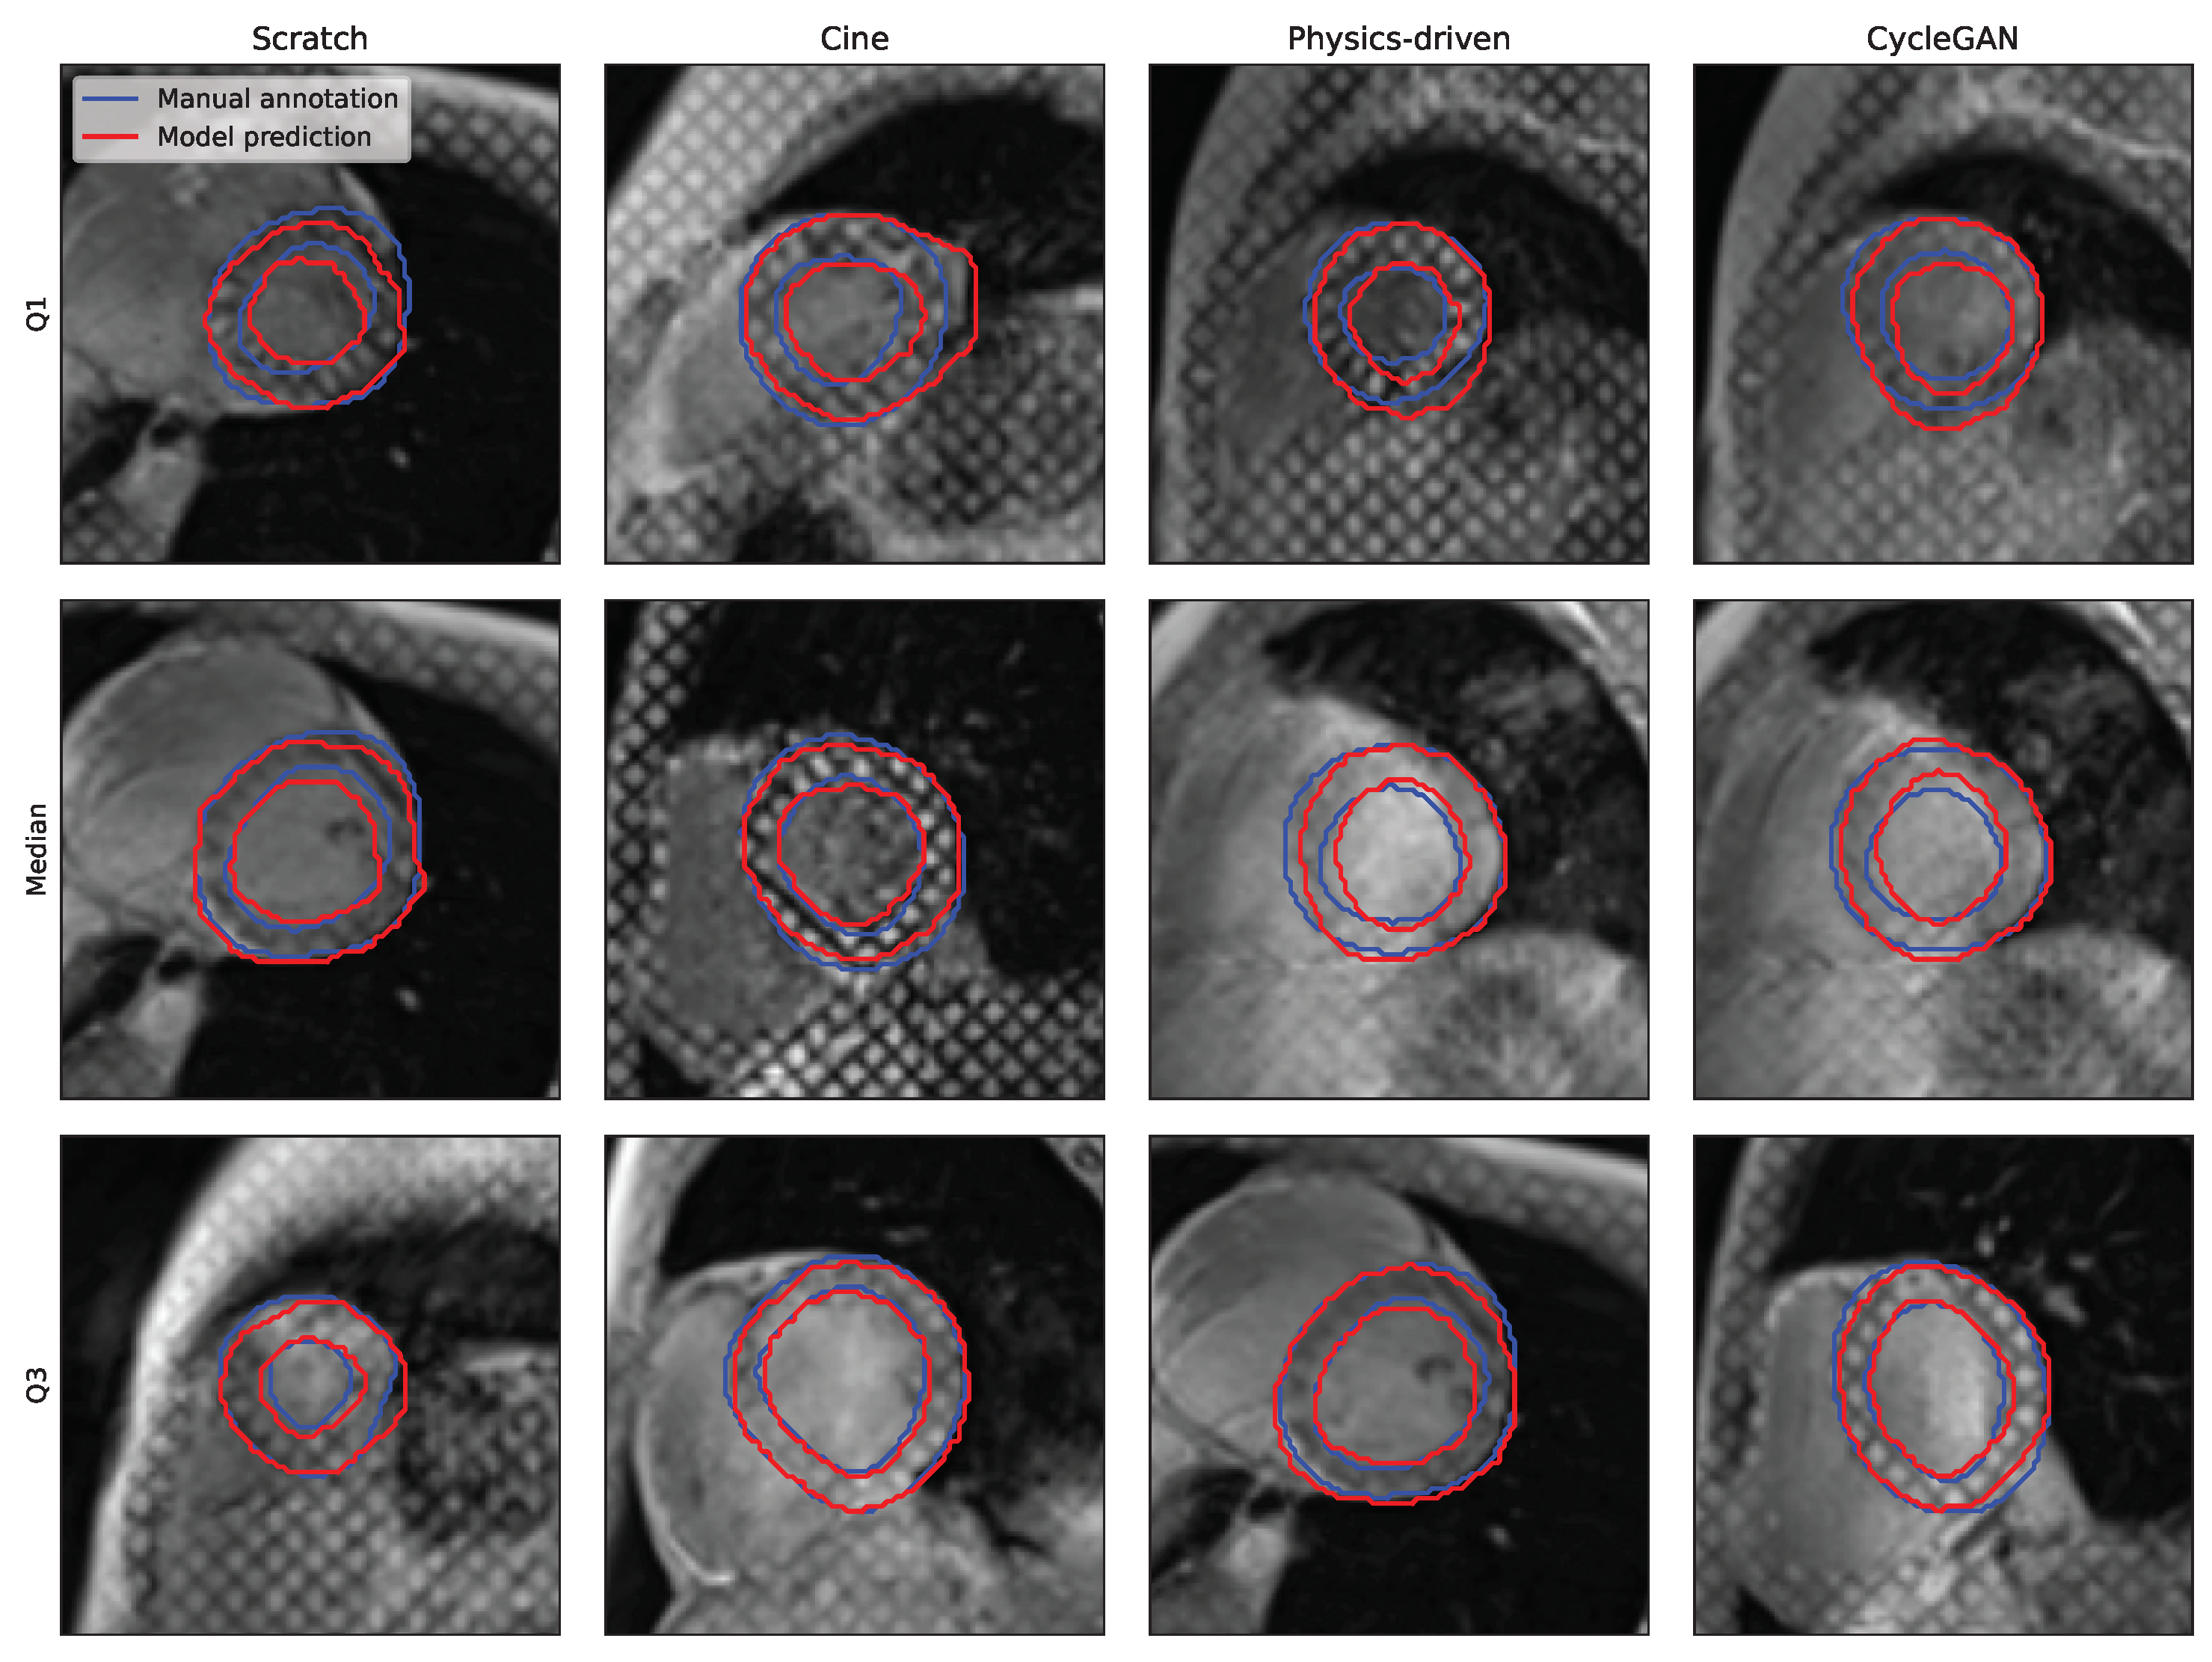

3.2.2. Training Strategies

3.2.3. Acquisition Time-Frame

4.1. Analysis of the Cine to Tagged Image Transformation Models

4.2. Analysis of the DL-Based Segmentation Network